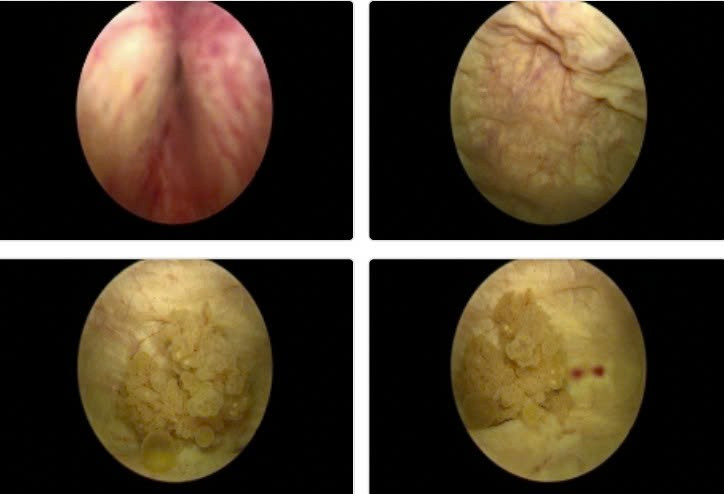

Hình ảnh nội soi u bàng quang vị trí sát lỗ niệu quản trái kích thước 2cm, có chỉ định phẫu thuật nội soi cắt u bàng quang sớm để chẩn đoán tế bào học - Ảnh BVCC

ut-bang-quang-1.jpg

Kết quả cắt lớp vi tính của người bệnh - Ảnh BVCC